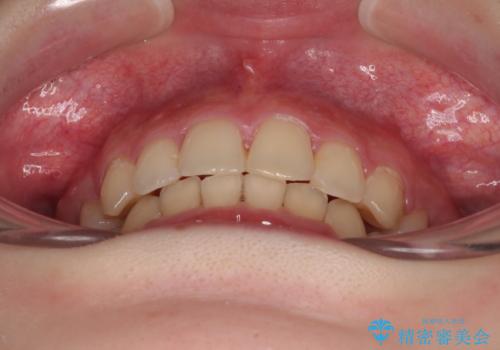

下の前歯が隠れてしまうほど深く咬みこんでいたため、上顎前歯が前方に突出しているような印象がありましたが、咬み合わせが改善され、整った口元に仕上げることができました。